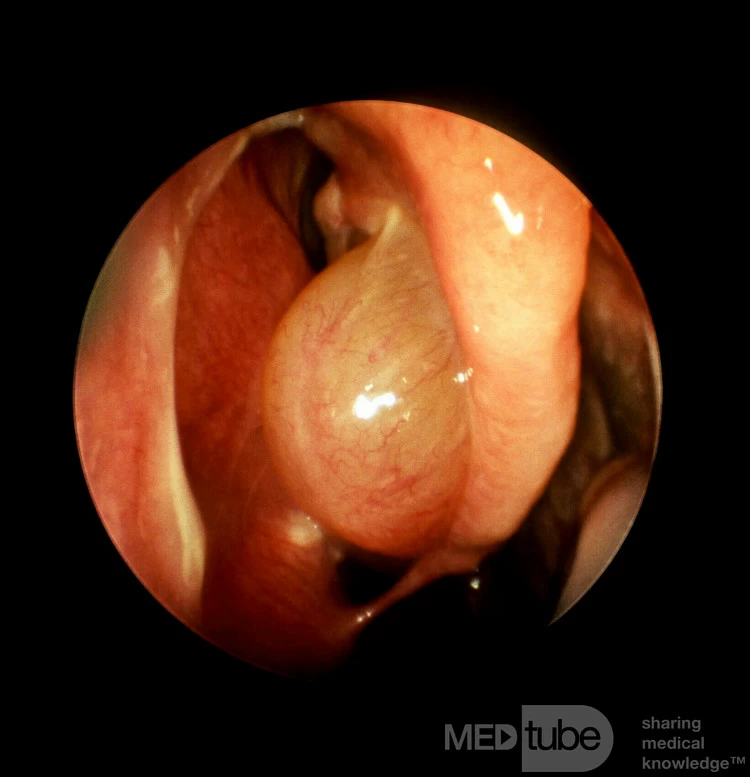

Polyp mũi xuất phát từ cuốn mũi giữa

Có một polyp đơn độc xuất phát từ bề mặt bên của cuốn mũi giữa bên phải này.